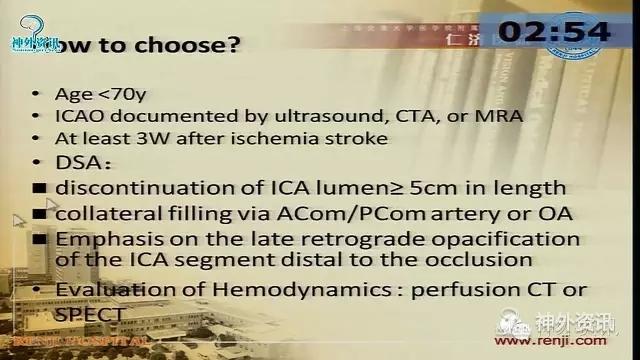

万杰清教授:慢性颈动脉闭塞再通技术及临床效果

擅长脑血管病的治疗研究工作,对动脉瘤性蛛网膜下腔出血的规范化、个体化治疗有独到之处,已成功治愈各种复杂性脑血管3000余例;擅长脑血管病的微创血管内介入和显微外科治疗,包括急性破裂出血的脑动脉瘤、脑血管畸形和硬脑膜动静脉瘘的栓塞治疗,以及颈动脉内膜切除和血管内支架治疗颈动脉狭窄预防脑梗死等。.曾获得仁济医院首届十佳青年,第二医科大学新长征突击手和优秀仁济人—白求恩式的好医生称号,2010仁济医院首届优秀青年临床骨干。分获上海市科技进步二等奖和三等奖。已发表论文30余篇,SCI收录7篇。